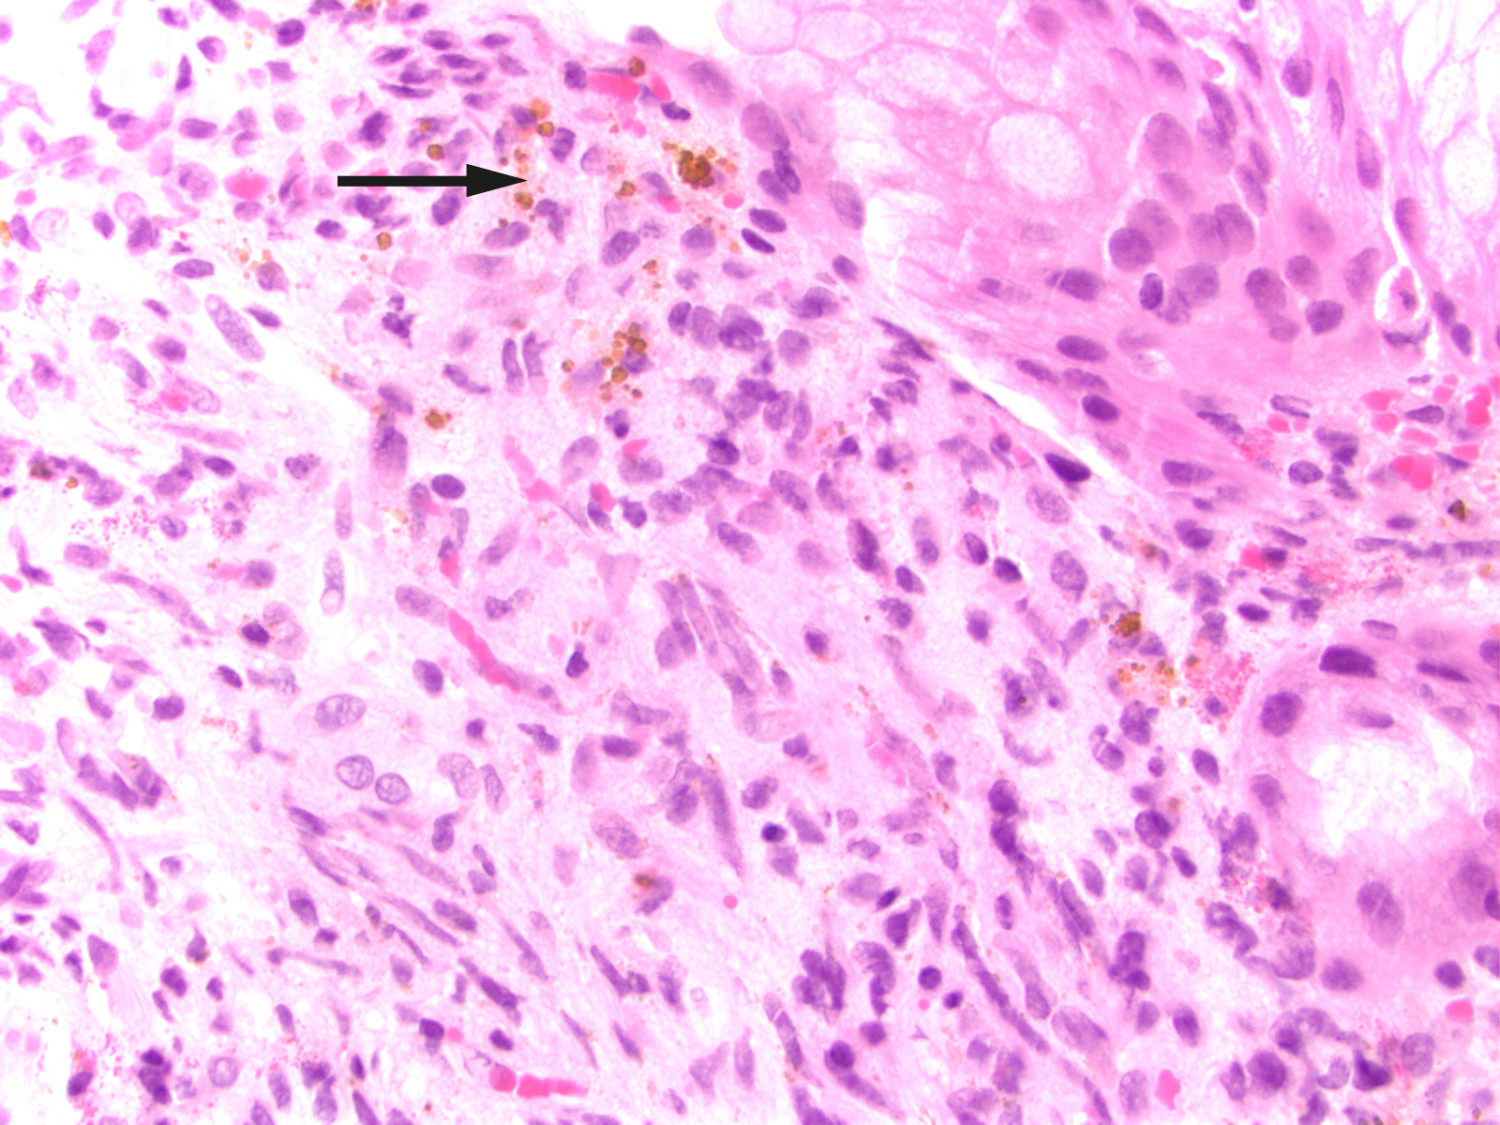

Etter denne episoden ble han ikke ordentlig bra. Han ble nok en gang innlagt og gastroskopert, og i ventrikkelen så man tre rødlige, puteformede forandringer med hemangiomaktig utseende. Forandringene ble biopsert. Ved sammenligning av makroskopisk gastroskopifunn med endoskopiatlas så man at funnet var patognomisk for gastrointestinalmanifestasjon av Kaposis sarkom (2). Patologen ble bedt om å undersøke ventrikkelbiopsier med tanke på dette. Pasienten viste også frem blålilla hudforandringer både på høyre underarm og venstre vrist som hadde økt i størrelse de siste fem månedene (figur 1). Hudforandringer på armen ble biopsert, og histologisk undersøkelse bekreftet Kaposis sarkom både i ventrikkel- (figur 2) og hudbiopsi. Begge biopsiene viste HHV-8-positivitet (humant herpesvirus 8). Lymfeknutebiopsien fra fem år tidligere ble revurdert til også å være forenelig med Kaposis sarkom (figur 3). Etter at diagnosen var stilt, ble det startet behandling med liposomalt doksorubicin intravenøst. På tross av behandlingen utviklet sykdommen seg videre med spredning til leveren, og pasienten døde litt over to år etter at diagnosen var stilt.

Kaposis sarkom er en multifokal, lavgradig, vaskulær tumor som involverer hud, mukosa og viscera (3). Sykdommen ble først beskrevet i fem kasuistikker av den østerrikske legen Moritz Kaposi i 1872, og han kalte tilstanden «idiopathic multiple pigmented sarcoma» (4, 5). I kasuistikkene beskrev han ødem og blålilla noduler på huden, mest på hendene og føttene. Ved mikroskopisk undersøkelse av hudbiopsier beskrev han små runde celler (spolceller), små hemorragiske områder med noduler og pigment (hemosiderin). Alle pasientene døde i løpet av to–tre år.

Histopatologiske funn er identiske ved de fire formene, og det typiske histologiske funnet er spolceller. Sykdommen progredierer i tre histologiske stadier: Det første kalles «patch stage» og er preget av flate, makuløse forandringer. Neste stadium kjennetegnes av plakk, mens det siste, tumorstadiet, preges av nodulære lesjoner. De histologiske forandringene kan lett oversees (5).